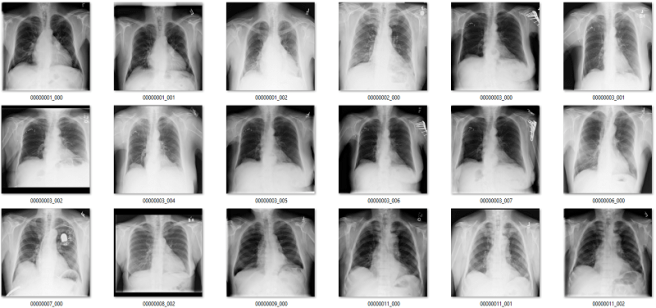

Complete nonsense as far as I can tell. Below are the model predictions, compared against the labels in the dataset. Again, the same technique as earlier for picking images. I’m confident these aren’t cherry picked.

True positives

The green ones are the only actual true positives. The rest have incorrect labels.

True negatives

There are one or two arguable ones in the top 18, but I gave the labels the benefit of the doubt. The red ones in the 2nd 18 are all wrong.

False positives

The red ones are wrong. It also turns out that there are rotated, inverted, distorted, and otherwise abnormal images in the dataset (shown by the red question mark). More on that in the next post.

False negatives

Again, the red ones are wrongly labelled.

Despite an apparent AUC of 0.7 we get really bad classification performance, in line with the label inaccuracy. The model didn’t just ignore the incorrect labels and produce sensible predictions. It was not robust to label noise. Most importantly, the AUC value does not reflect the clinical performance.

This is a huge problem.

This AI system learned to reliably produce meaningless predictions. It managed to learn image features that create the above groups of “opacity” cases with almost no airspace opacities, and “no opacity” cases with big groups of severely abnormal lungs.